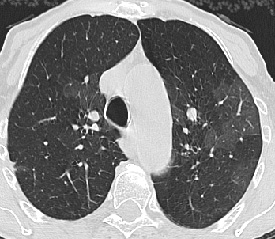

CT/HRCT

• Directly visualize clot in central pulmonary artery

• CT angiograms highly sensitive and specific

• Mosaic perfusion, usually less well defined than pattern with small airways disease

• Due to vascular obstruction with areas of hypoperfusion and overperfusion

• No air trapping with expiratory scanning